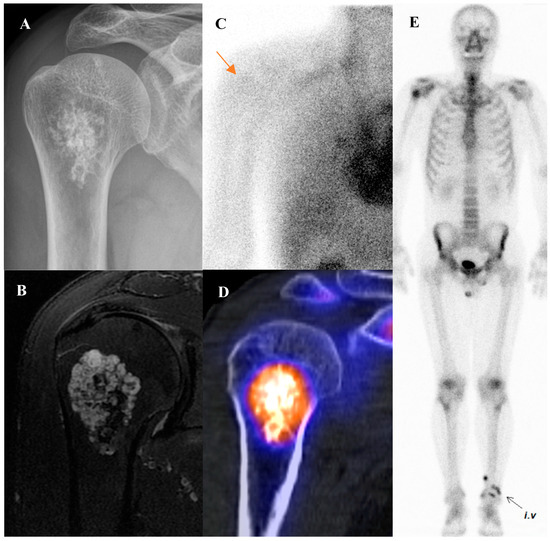

Current Position of Nuclear Medicine Imaging in Primary Bone Tumors

Primary bone tumors encompass a heterogeneous spectrum ranging from benign entities to highly aggressive sarcomas. This review aims to summarize the current role and future perspectives of nuclear medicine in the diagnosis, staging, and management of primary bone tumors. Accurate diagnosis and staging [...] Read more.

Primary bone tumors encompass a heterogeneous spectrum ranging from benign entities to highly aggressive sarcomas. This review aims to summarize the current role and future perspectives of nuclear medicine in the diagnosis, staging, and management of primary bone tumors. Accurate diagnosis and staging are critical yet challenging due to histologic heterogeneity and overlapping imaging features. While radiographs, computed tomography (CT), and magnetic resonance imaging (MRI) remain essential, nuclear medicine provides a complementary functional perspective by assessing bone turnover, vascularity, and glucose metabolism. Bone scintigraphy is highly sensitive for skeletal lesions and useful for detecting skip lesions or multifocal disease, although its specificity is limited. Hybrid single-photon emission computed tomography (SPECT)/CT enhances diagnostic confidence through precise anatomic localization and quantitation. [18F]fluorodeoxyglucose ([18F]FDG) positron emission tomography (PET)/CT, by directly visualizing tumor metabolism, has become a cornerstone in osteosarcoma and Ewing sarcoma management, demonstrating superiority over bone scintigraphy for detecting skeletal metastases. In chondrosarcoma, [18F]FDG uptake correlates with histologic grade, although overlap with benign cartilage tumors complicates interpretation. Future directions include the integration of quantitative SPECT, artificial intelligence, and novel tracers such as [18F]sodium fluoride and [68Ga]Ga-fibroblast activation protein inhibitor (FAPI). Collectively, nuclear medicine imaging is becoming a key element in musculoskeletal oncology, offering unique biological insights that complement anatomic imaging and contribute to improved patient management. Full article

Show Figures

Figure 1